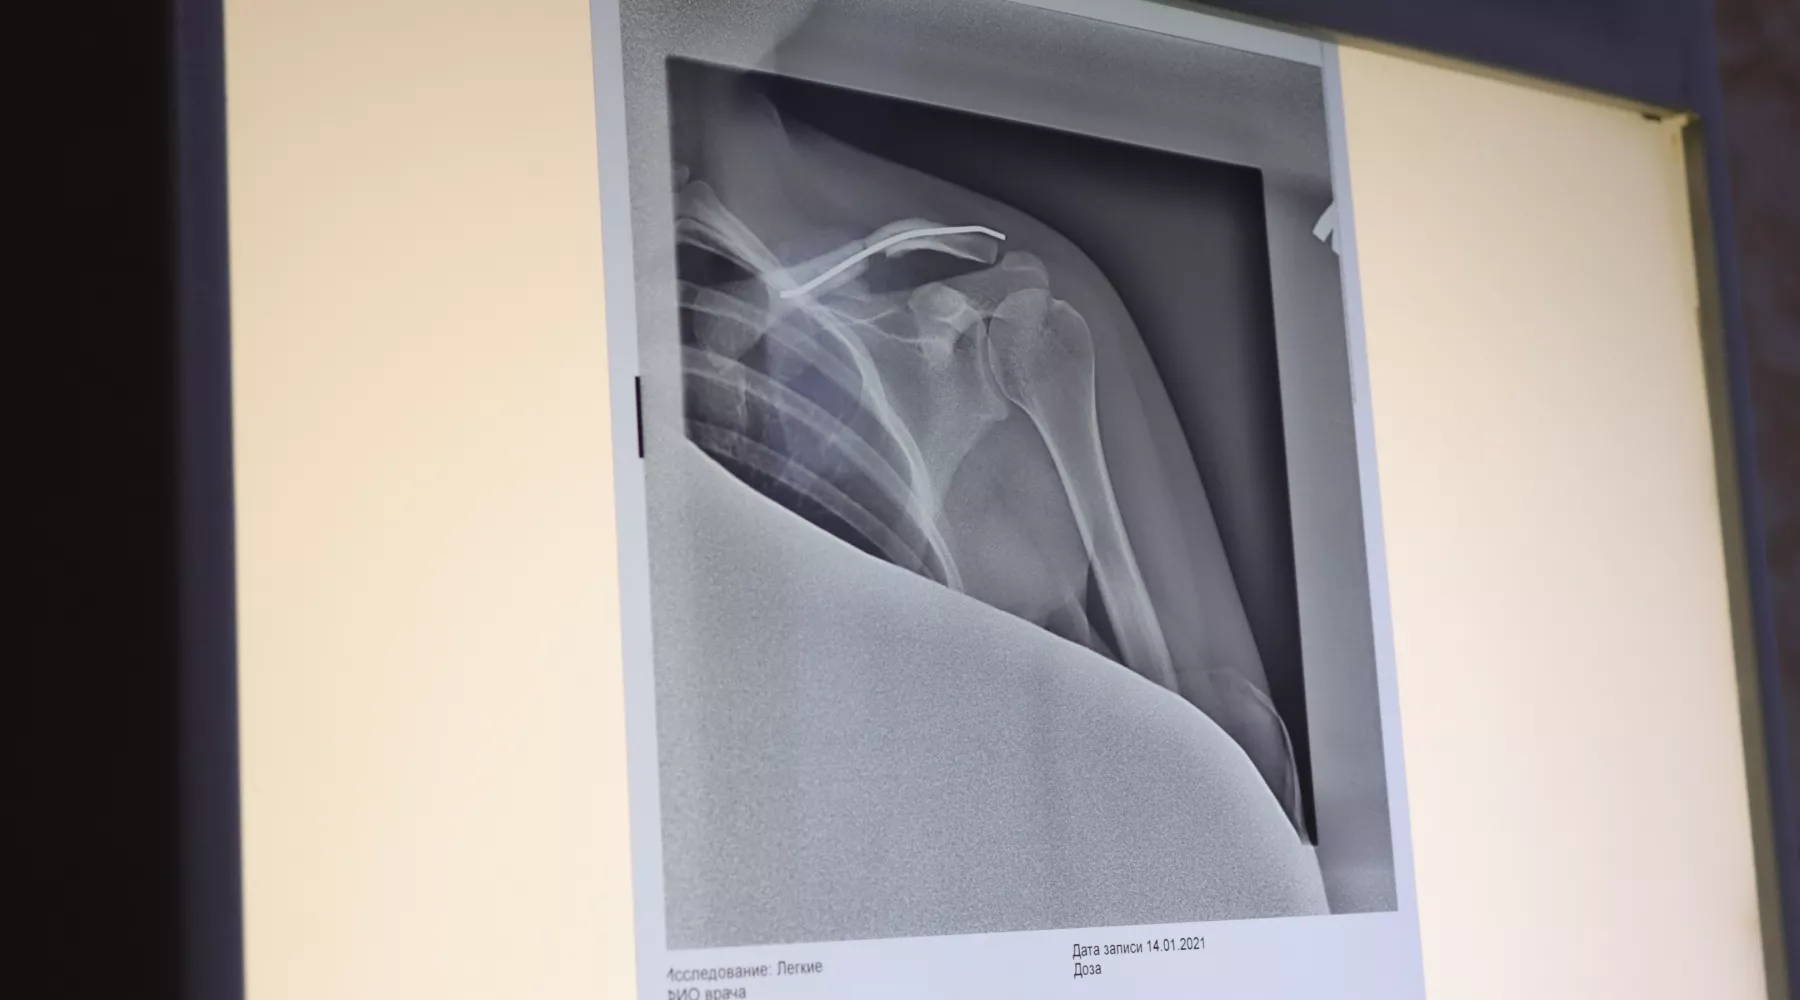

Рентген показал патологический перелом в правом плече, что означало — перелом вызван не травмой, а болезнью. Школьнику сделали биопсию, которая подтвердила остеосаркому. В плече образовался свищ, и только после его лечения и химиотерапии мальчик попал на операцию в московский НМИЦ онкологии, иммунологии и гематологии имени Дмитрия Рогачева. Мальчика поддержали родные и близкие, учителя и одноклассники, ему помогали благотворительные фонды «Подари Жизнь» и « «Защити Жизнь».

«Операция была очень сложная, она длилась более 5 часов. Хирурги удалили мне пораженные кости в правом плече и в лопатке. Вместо них установили титановый протез. Ремиссия продлилась месяц, но остеосаркома вернулась. Уже в Новосибирске продолжились курсы химиотерапии, следующие два с половиной года я ложился в больницу, месяц проводил там и всего несколько недель дома», — рассказал Руслан.

«Руслан сохранил подвижность рук, но поднять их выше груди не может, они плохо работают, особенно правая. На правой руке было 5 операций, меняли протезы, потом опухоль спустилась ниже, и сыну заменили правый локоть. Частично удалили правое ребро, всего было 10 операций. Стабильно два раза в год мы ездили в клинику Рогачева на операцию», — рассказал Виталий, отец Руслана.